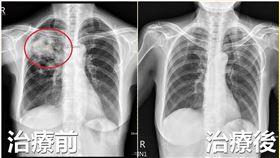

咳到不行不是感冒 肺部竟被啃了一個洞

喘咳以為只是感冒,想不到肺部被吃了一個洞!65歲的王...

台中女狂喘咳疲倦無力 肺部遭細菌啃破洞

一名65歲王姓婦人,因卵巢癌接受化療,治療一個多月後...